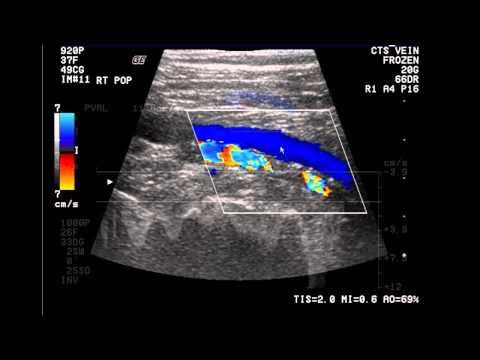

An elderly gentleman presented with swelling of feet since few months. Known hypertensive and Parkinson's disease on treatment. Evaluated. No evidence of cardiac failure. Normal kidney/liver function. Not on Amlodepine.(which can cause edema). Doppler study LL vein done. #edema

Your doctor will take your medical history and give you an exam. You may also have an imaging test called a Duplex ultrasound. This looks at blood flow and the structure of your leg veins. It checks the speed and direction of blood flow in the blood vessel.